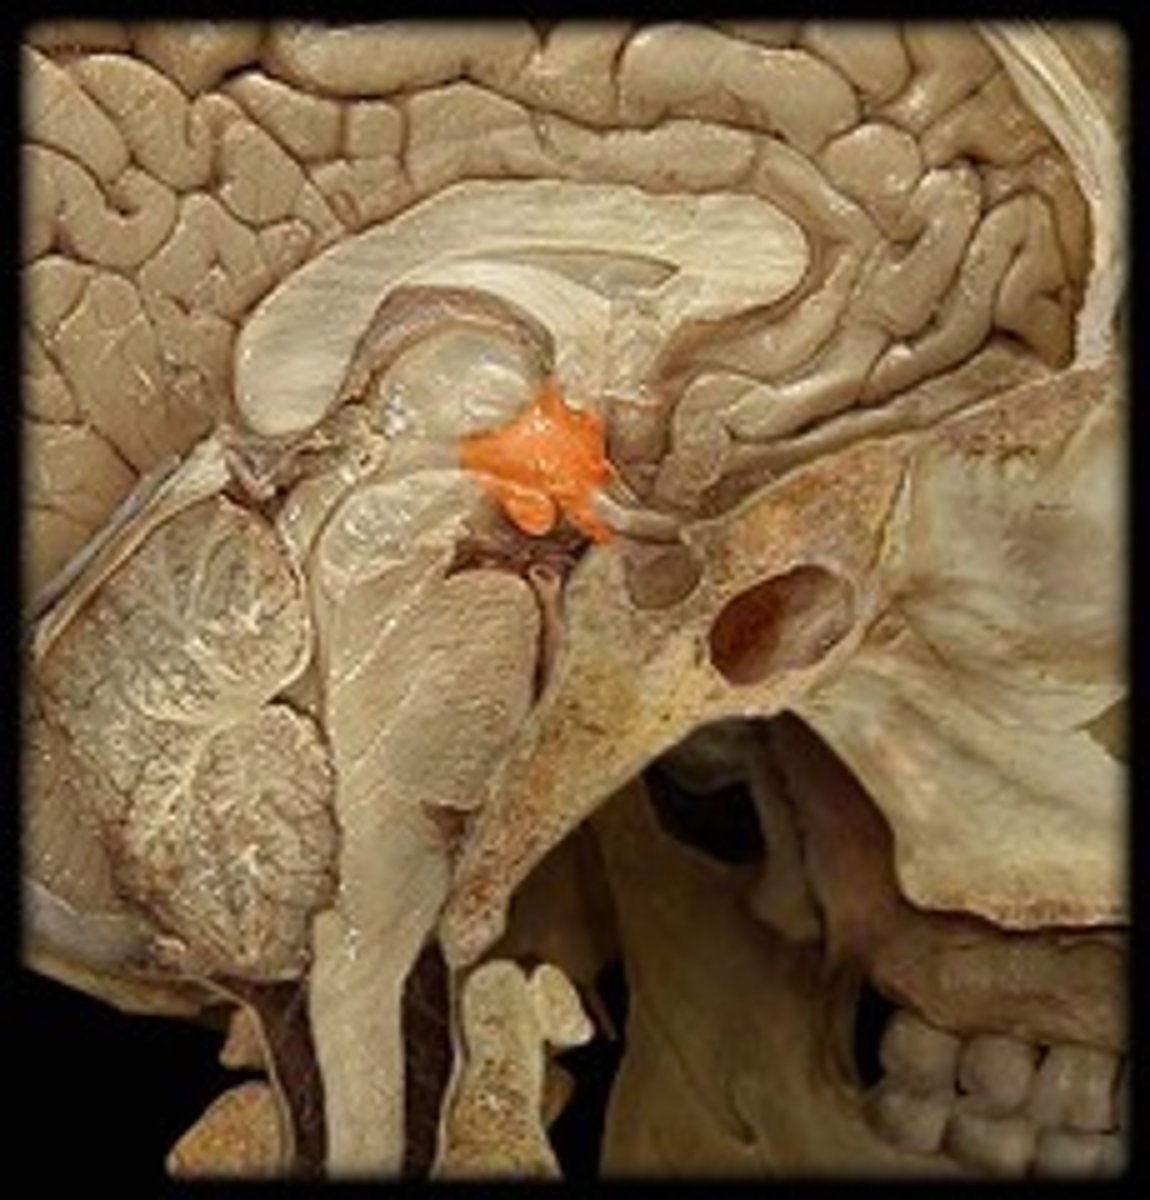

MIdsagittal View of brain

Pineal Gland

Hypothalamus